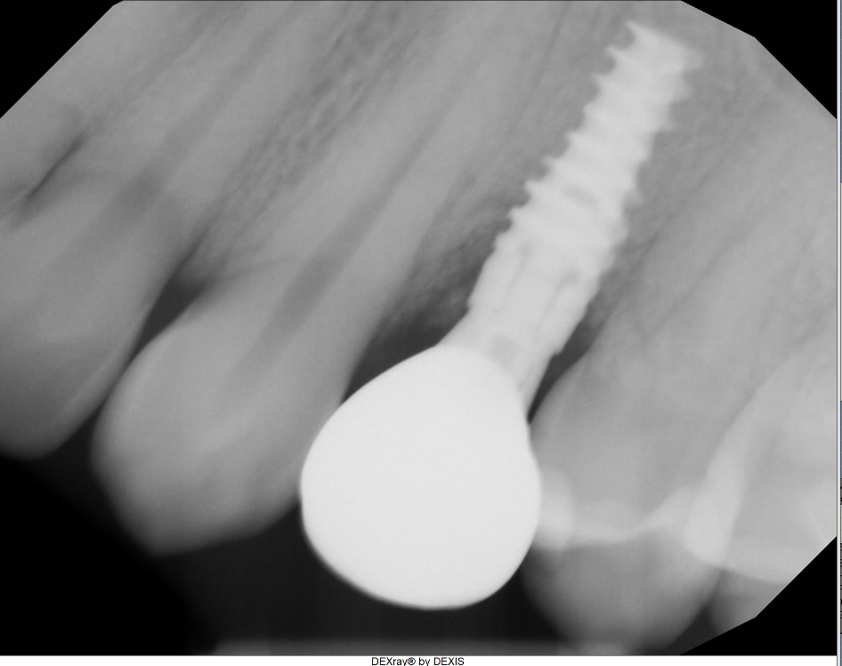

Peri-Implantitis Rescue

Implant #12

Challenge: Patient presented with severe peri-implantitis on implant #12, exhibiting 50% radiographic bone loss, deep pockets, and inflammation.

Solution: Laser-assisted surface decontamination and regenerative bone grafting to salvage the fixture without explantation.

Outcome: 100% radiographic bone regeneration achieved with complete resolution of inflammation and stable soft tissue attachment.